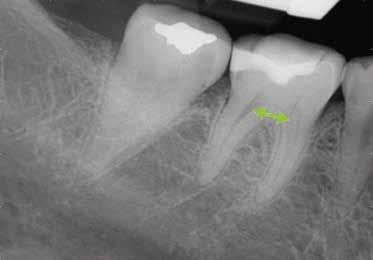

Egy 38 éves nőbeteg a korábban kezelt jobb felső második kisőrlőfogából (1.5) kiinduló mérsékelt fájdalom miatt jelentkezett rendelésünkön. A kórtörténetében jelen panasza szempontjából releváns információ nem szerepelt. A beteg a klinikai vizsgálat során vertikális kopogtatásra enyhe érzékenységet jelzett. A kérdéses fog körül mérhető szondázási mélység és a fogmobilitás fiziológiás volt. Periapicalis röntgenfelvételen egy, a fog gyökércsúcsán túl presszálódott betört gyökérkezelő műszerből származó eszközfragmentumot láttunk (2. a. ábra). A preoperatív CBCT-felvétel a buccalis csontlemez épségét igazolta (2. b-c. ábra). A fog revíziója öt hónappal korábban történt. A már előzőleg gyökérkezelt, gyökértömött, majd revideált 1.5-ös fog esetében a diagnózisunk periodontitis periapicalis symptomatica volt. A periapikális elváltozás kezelése érdekében navigált endodonciai mikrosebészeti beavatkozást végeztünk.

A felső állcsontról intraorális szkent (TRIOS) készítettünk, és az ezáltal kapott STL fájlt (2. d. ábra) a CBCT-felvétel során nyert DICOM fájlokkal a Zirkonzahn.Implant-Planner (Zirkonzahn) szoftverben egyesítettük. A sebészi sablont ebben a programban megterveztük, majd a Meshmixer (Autodesk) szoftver se-

gítségével tovább módosítottuk. Az így kapott sebészi sablon egyértelműen meghatározta a periapikális terület eléréséhez szükséges csontablak határait (2. e-f. ábra) Helyi érzéstelenítést követően teljes vastagságú mucoperiostealis lebenyt képeztünk, majd a buccalis csont feltárását követően (2. g. ábra) a sablon segítségével bejelöltük a preparálandó csontablak határait (2. h. ábra). A csontablak kialakítása során Piezotome CUBE LED kézi-darabot alkalmaztunk, majd a leemelését követően a betört eszközt megkerestük (2. i. ábra) és eltávolítottuk (2. j. ábra). A rezekciót ultrahangos megmunkáló fejekkel (ACTEON) végeztük, majd retrográd preparáció következett.

A retrográd gyökértömés elkészítése során TotalFill BC RRM Fast Set Putty-t (FKG) használtunk (2. k. ábra). A lebeny széleit 5/0-s Prolene varratokkal egyesítettük (2. l. ábra). A varratok a műtétet követően 72 órával kerültek eltávolításra. A beteg két évvel később kontrollröntgen készítése céljából érkezett rendelőnkbe. A vizsgálat során a fog tünetmentesnek és funkcióképesnek bizonyult (2. m. ábra).